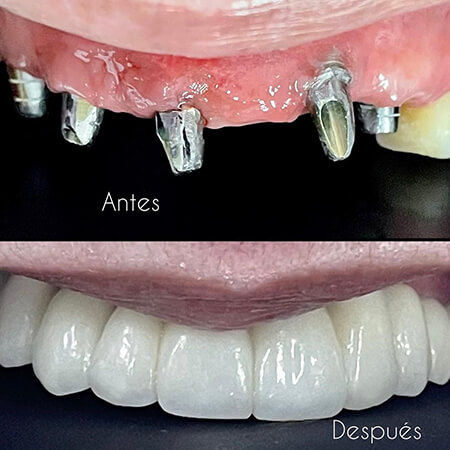

CFC Carlos Fernández De Castro

Dentist Barranquilla

Oral rehabilitation treatment with dental implants and fixed prosthetics at the CFC Carlos Fernández De Castro Clin…